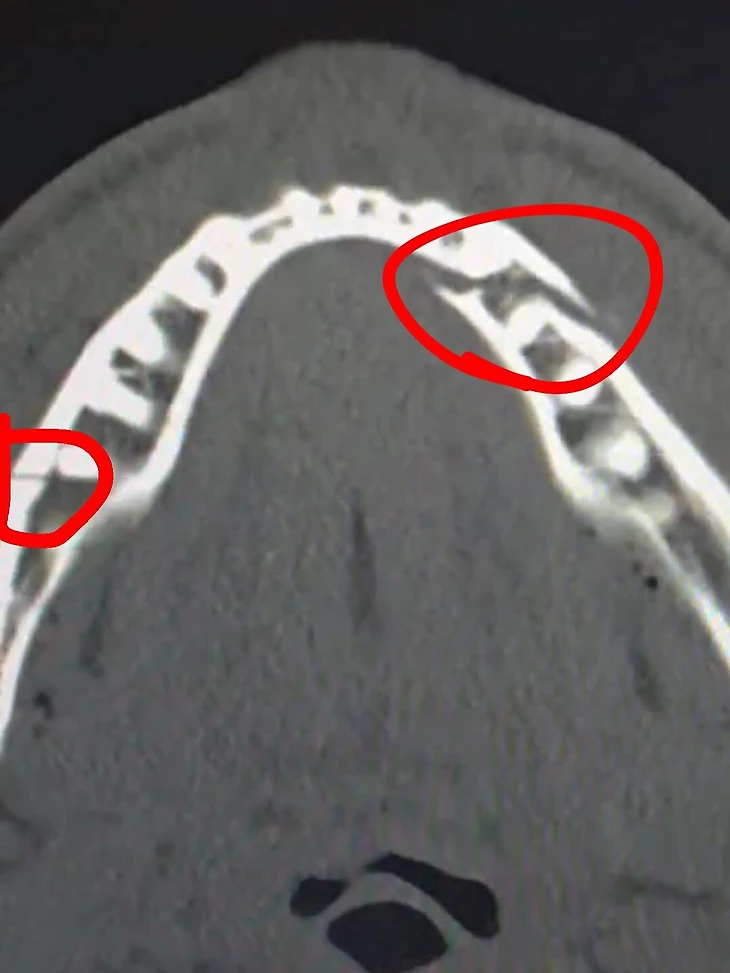

На интервью после боя Пол осознал, что у него сломана челюсть: «Да, она точно сломана. Но ничего – так тоже бывает». Потом показывал зубы в крови:

«Джейк сломал челюсть, – заявил руководитель Most Valuable Promotions Накиса Бидариан. – Что касается остального, то с ним все в порядке. После боя мы встретились с представителями Netflix, затем он принял душ и сам поехал в больницу.

Перелом челюсти – довольно распространенная травма в спорте, особенно в боксе и ММА. По оценкам врачей и хирургов, с которыми мы уже пообщались, восстановление займет от четырех до шести недель».

Уже из больницы Пол показал снимок: